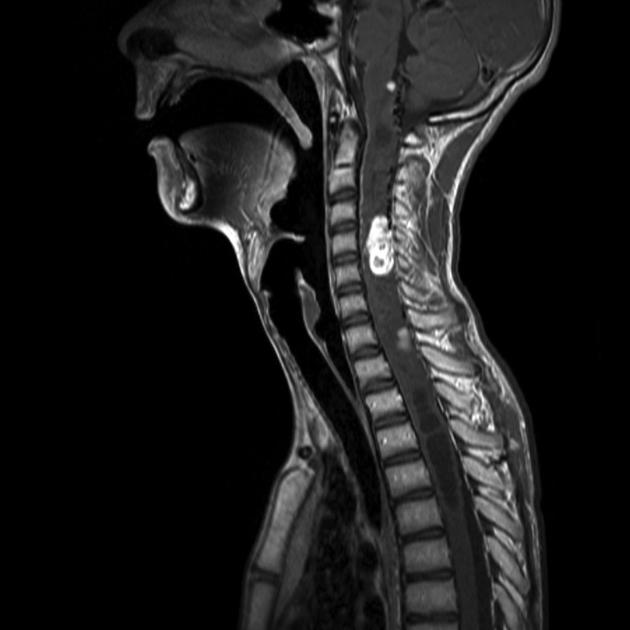

imaging findings in intracranial hypotension

sagging brainstem

downward displacement of cerebellar tonsils

slit ventricles

diffuse pachymeningeal (dural) enhancement

subdurals, can be bilateral

chiari malformation

I: downward displacement of cerebellar tonsils, often associated with syringomyelia